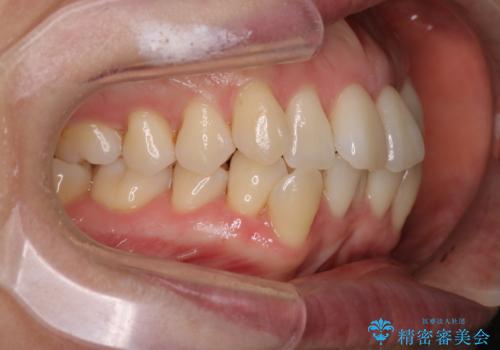

【抜歯ケース】前歯のガタガタをインビザラインで治療

- 前歯のガタガタを主訴に来院されました。

抜歯が必要なケースでしたが、インビザラインでの治療を希望されワイヤーを使用せずに治療を完了しております。

抜歯を伴う矯正治療はマウスピース矯正よりもワイヤー矯正の方がメリットが多いです。当院で抜歯を伴うマウスピース矯正を希望される場合は、場合によってワイヤーを使うことを了承していただいた上で治療を行なっています。